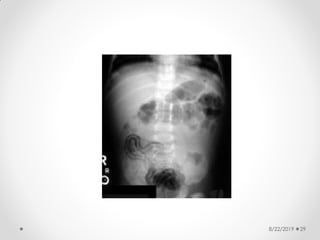

Pneumatosis intestinalis

8/22/2019 28

8/22/2019 29

Abdominal X-ray

findings:

• Dilated bowel loops

• Thickened bowel wall

• Fixed dilated loop

• Scarce or absent intestinal gas

• Pneumatosis intestinalis:

• radiologic sign pathognomonic of NEC

• appears as a characteristic train-track

lucency configuration within the bowel wall